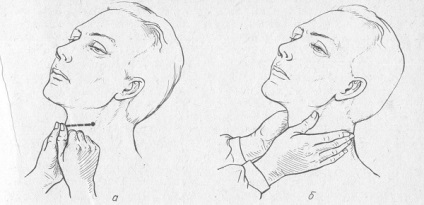

Csökkenti a szívfrekvenciát lehet egy kis masszázs. Szükségessé teszik, óvatosan lenyomva a jobb oldalon a nyak (arteria carotis van) 5 percig.

Masszázs a verőér

Ez a gyakorlat bosszantó nyomás receptorok az edényben, ami annak kiterjesztését, a vérnyomás csökkenését. De ez lehetetlen alkalmazni masszázs az idősek, mert ez is okozhat számukra a stroke.